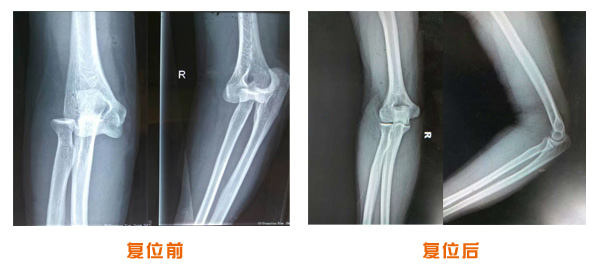

肥城市安駕莊梁氏骨科醫(yī)院是一所以梁氏手法正骨配合膏藥為特色的現(xiàn)代化??漆t(yī)院。

梁氏骨科術(shù)始創(chuàng)于清雍正年間,歷經(jīng)八代,至今已有三百年歷史。據(jù)1929年泰安縣志載“梁瑞圖先生,字增生,號蓮峰,安駕莊人,精岐黃并發(fā)明接骨,凡跌打車凡跌打車軋皮不破而碎骨者......【詳細】 |